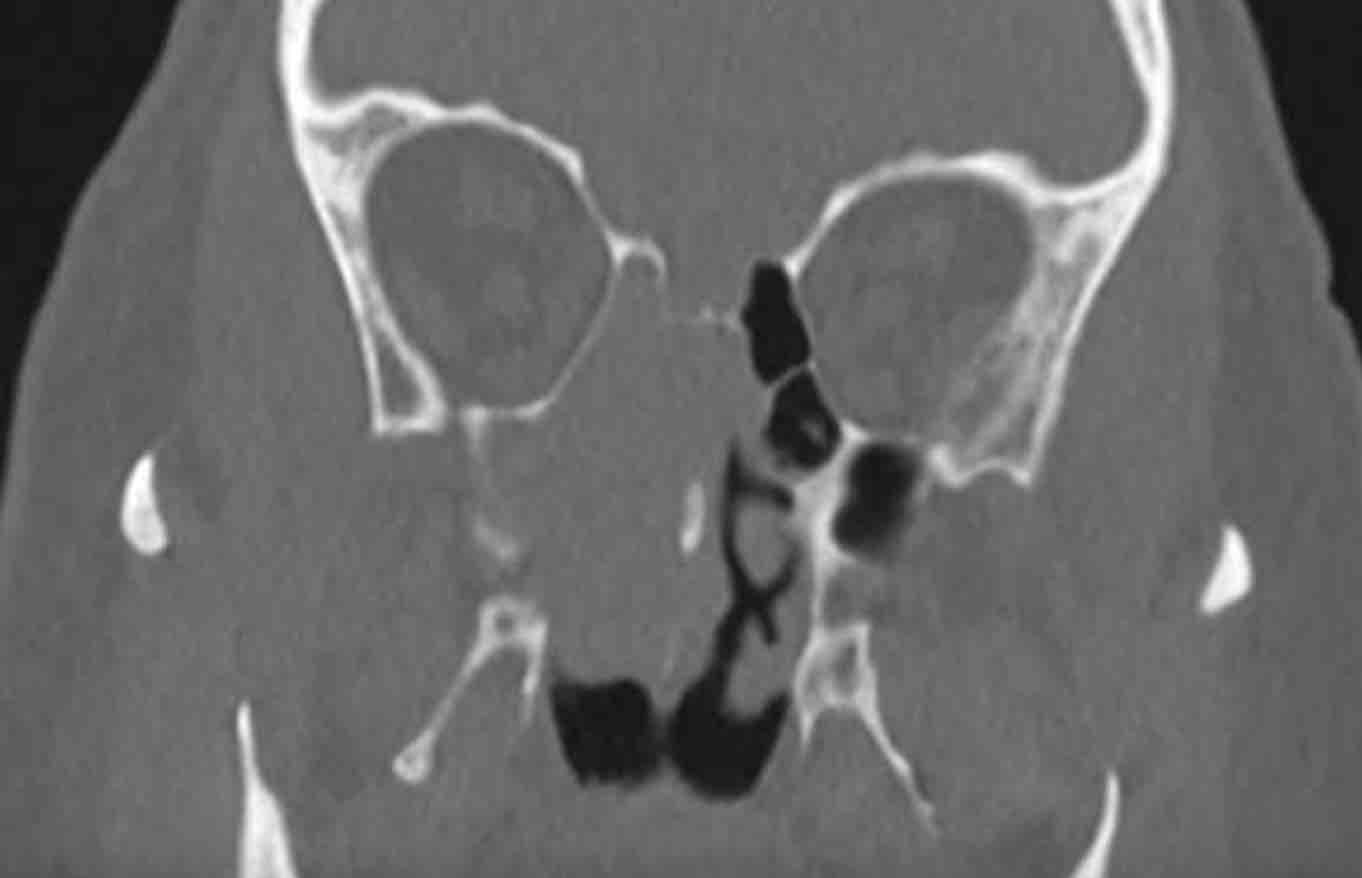

Các hình ảnh này của bệnh nhân nam 75 tuổi có triệu chứng nghẹt mũi và chảy máu mũi.

Hãy quan sát các hình ảnh trước.

Tiếp tục với các tái tạo mặt phẳng coronal…

Cuộn qua các hình ảnh.

Các dấu hiệu hình ảnh là gì?

Tổn thương có kiểu giãn rộng hay phá hủy (dấu hiệu cảnh báo)?

Có dấu hiệu cảnh báo nào khác không?

Hai dấu hiệu cảnh báo là:

- Phá hủy thành trong xoang hàm (mũi tên đen) và vách mũi (mũi tên trắng).

- Bệnh lý hoàn toàn một bên.

Ở bệnh nhân viêm mũi xoang, có thể có giãn rộng và đôi khi thậm chí phá hủy xương, nhưng bệnh lý (hầu như) luôn luôn xảy ra hai bên.